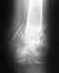

30 августа был на консультации НИИ травматологии у травматолога Медведевой, пожаловался на субфебрильную температуру. 3 месяца прошло, 2 срока после остеосинтеза. Металоконструкция убрана 17.08 в госпитале ветеранов войн т.к спица пробила сустав. Мне сделали КТ. Сказали, что остеомиелита нет. Диастаз при разогнутой руке 3 мм. Костных балок нет, есть хрящевая ткань по краям. Руку не фиксировали, сказали ограничить физические нагрузки. Работаю врачом неврологом в Первоуральске. Пишу, печатаю, осматриваю пациентов. Субфебрильная температура держится если нужна повторная операция, я согласен платно. Сколько это стоит и как практически это сделать в НИИ травматологии. Подскажите очень буду благодарен, не знаю, что делать?